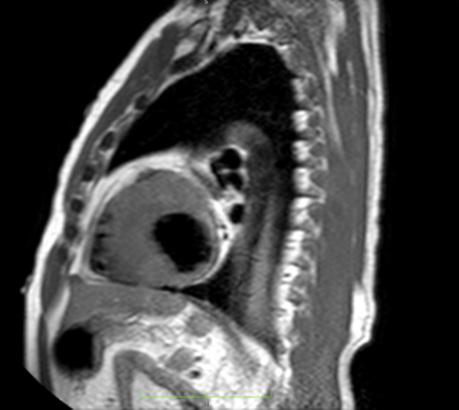

Figure 1: Vista coronal de resonancia magnética cardíaca IVS engrosamiento 3,0cm e infiltración fibrosa septal.

• La resonancia magnética cardíaca

Cardiovascular Disease Fellowship Program, St. Figure 2: Vista sagital de la resonancia magnética cardíaca IVS engrosamiento de 3,0 cm e infiltración fibrosa septal.

posterior mostró un engrosamiento del tabique interventricular de 3,0 cm, así como una infiltración fibrosa del tabique confirmando el diagnóstico de MCH.